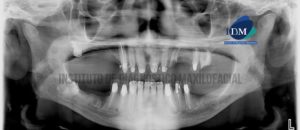

Paciente sexo femenino de 55 años acude al Instituto de Diagnóstico por Imágenes para evaluación imagenológica previa a la confección de guía quirúrgica. A la